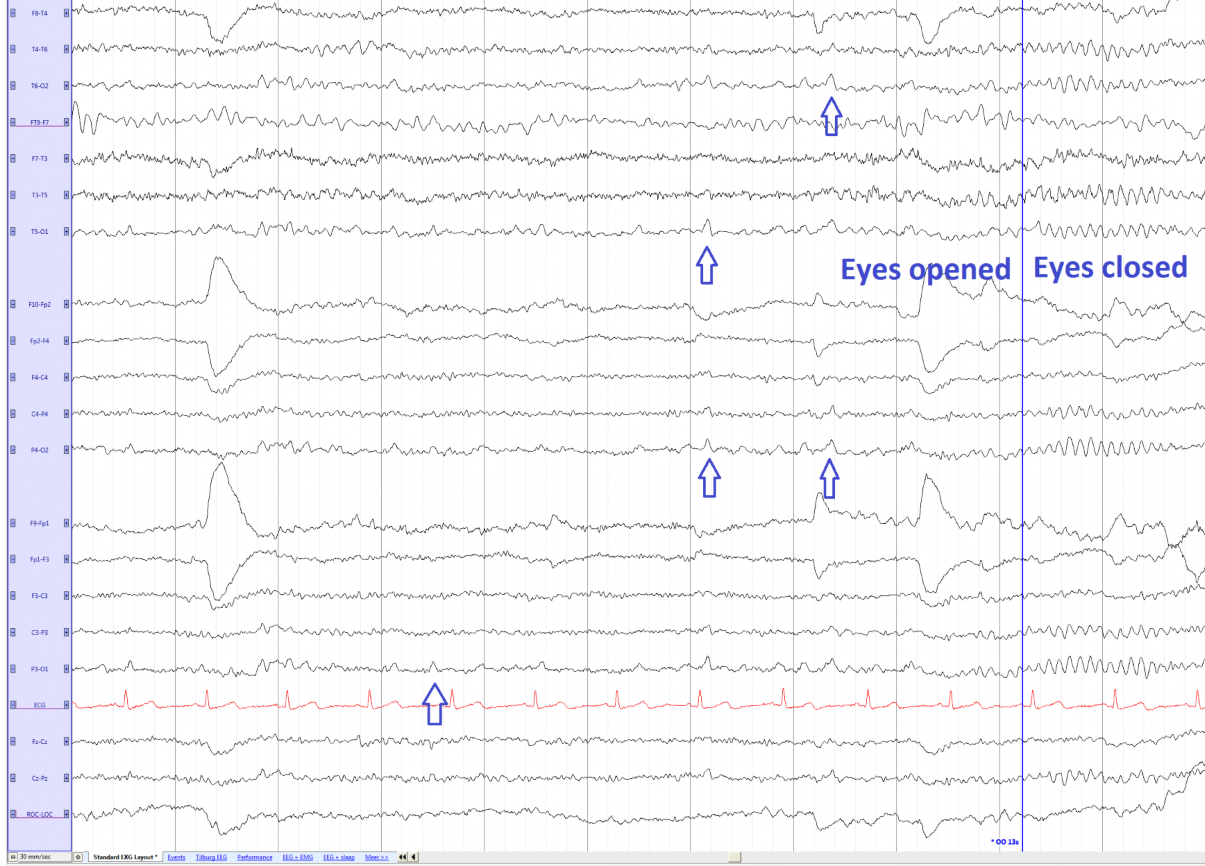

O que é o Ritmo Mu?

A

Ritmo fisiológico que ocorre durante a vigília, com frequência e amplitude semelhantes ao ritmo alfa, mas com morfologia, topografia e reatividade diferentes.

Visualizado em uma minoria das pessoas, mais prevalente em adolescentes e adultos jovens, podendo ser identificado a partir dos 2 anos de idade, com pico entre 11 e 15 anos.

18

Q

Quais são as características topográficas do Ritmo Mu?

Predomina na região central, podendo atingir áreas parietais, especialmente nos eletrodos C3 e C4, e também pode se estender para a região do vertex (Cz).

A amplitude do Ritmo Mu é semelhante à do ritmo alfa.

19

Como é a morfologia do Ritmo Mu?

Arciforme, com uma fase negativa pontiaguda seguida de uma fase positiva arredondada, em forma de arco.

Bloqueado principalmente pelo movimento, fadiga e estímulo sensitivo, e não sofre alteração com abertura ocular.